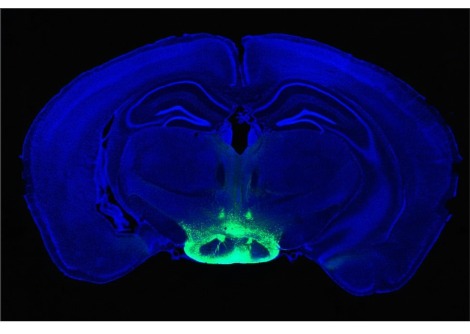

في البحث الجديد، شرع العلماء في تحديد السبب الذي أدى إلى حجب مستقبلات هرمون الاستروجين في منطقة ما تحت المهاد في إناث الفئران ذات الكثافة العظمية العالية بشكل خاص . بالمقارنة مع الفئران الطبيعية ، فإن الفئران الطافرة "كان لديها عدد متزايد بشكل ملحوظ من الخلايا الجذعية العظمية"، كما يقول عالم بيولوجيا الخلايا الجذعية توماس أمبروسي من جامعة كاليفورنيا، ديفيس .

ثم أضاف العلماء هذه المواد إلى الخلايا الجذعية للفئران في طبق بتري، واكتشفوا أنه عند معالجتها بـ CCN3، تتشكل أجزاء من العظام . ووجد الفريق أيضًا أن مستويات CCN3 ارتفعت لدى إناث الجرذان أثناء الرضاعة ، مما يشير إلى أن CCN3 يلعب دورًا في دعم قوة عظام الأم أثناء الرضاعة الطبيعية ، عندما تنخفض مستويات هرمون الاستروجين .